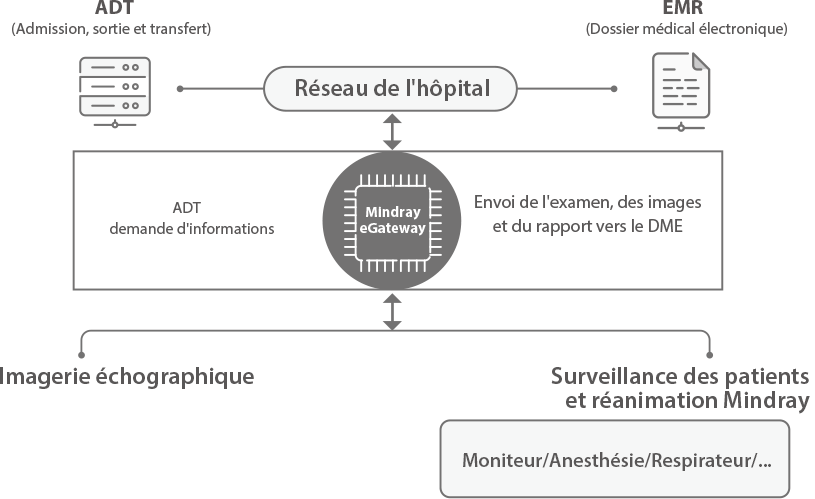

L'├®chographe TE9 a ├®t├® con?u pour faciliter les soins et ├®tendre les capacit├®s d'imagerie pour lŌĆÖanesth├®sie, les urgences et les soins intensifs. Gr?ce ├Ā ses fonctions avanc├®es, son grand ├®cran tactile et sa technologie d'imagerie sup├®rieure, l'├®chographe TE9 permet d'am├®liorer l'efficacit├® clinique et dŌĆÖassurer un diagnostic en toute confiance. Gr?ce ├Ā des outils dŌĆÖacquisition et de calculs automatiques, les soignants peuvent obtenir des mesures rapides et reproductibles dans le cadre d'examens et proc├®dures fiables, m├¬me dans des environnements o├╣ le rythme est soutenu.